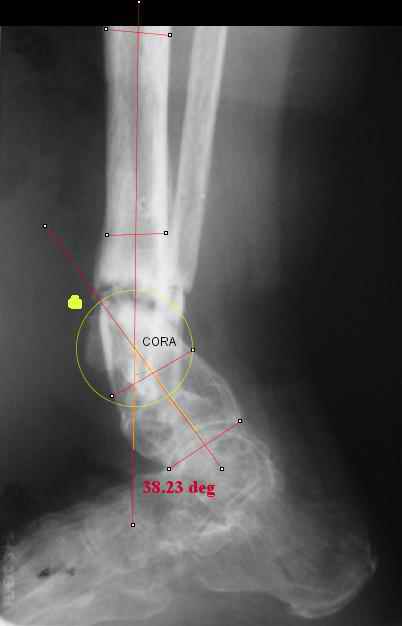

I played with your image using some orthopedic software we have been developing for digital

image analysis.

What you see marked up is the intercept of two mid-line tool centre lines, used to define the CORA. An angle tool gives the angular deformity and a circle tool is applied to show that a correction around the CORA through the old # will restore alignment without much translation.

TDVC> I played with your image using some orthopedic software

TDVC> we have been developing for digital image analysis.

I definitely have to learn more about this. THX in advance.

TDVC> a correction around the CORA through the old # will restore

TDVC> alignment without much translation.

Maybe my "embedded software" is obsolete but it hints me to place hinges at the yellow point - this must result with alignment and some lengthening without translation. What do you think?

Hello Alex:

Did you like what you saw from the mark-up on your figure?

We will be looking for some Beta site users of the software (no charge for use but looking for feed-back and for suggestions on needs). Would you be interested in that?

Re the CORA.:

I think that if you locate the hinge at that site and then you rotate the foot about this point with out distraction you will be perfectly lined up. If you distract in the axis of the proximal tibia then rotate, it should still work (the hinge should still be located in the mid tibial axis). But, if you distract out of that axis then you will get translation. Does that make sense?

Regards

Derek

Отправитель: T. Derek V. Cooke 15 Апрель 2005, 22:05

Hi Alex:

I looked at your image. I presume your yellow marker is the hinge axis? I think this should be at the CORA.